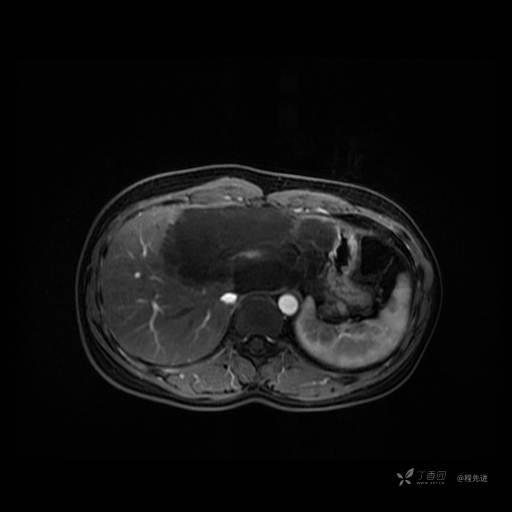

MR平扫+增强

每个序列一张图像(图像太多了,恕不一一发上来)